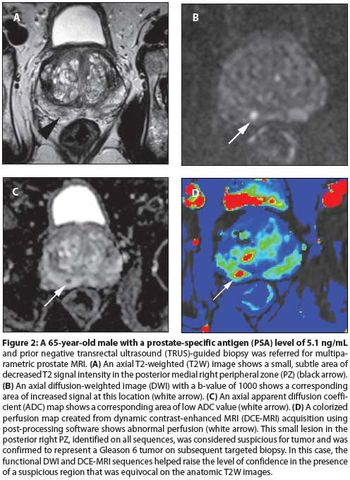

The concept of multiparametric MRI comes at an important time in the history of prostate cancer screening. It is a method that provides anatomic information about the location, number, size, and risk of prostate cancers. It permits more accurate targeted biopsies that will improve the quality of tissue obtained, thereby reducing the rate of upstaging associated with random biopsies.

Multiparametric MRI is a promising tool for identifying cancer within the prostate. It has the potential to drastically change the way prostate cancer is staged and treated. However, work remains to make this technique reproducible and accessible to the community-based radiologist and urologist.

Only the possibility of increasing survival with better tumor localization and staging is probable with multiparametric MRI-and improved survival with MR imaging in prostate cancer has not been shown in a clinical trial or meta-analysis to date.

Our aims in this article are to describe the various imaging sequences that comprise the multiparametric MRI exam, as well as to review current literature on the strengths/weaknesses of these sequences; to delineate strategies for standardizing interpretation and reporting of MRI results; and to expound on the role of prostate MRI in clinical practice.